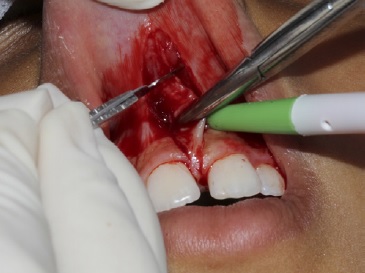

Em seguida, foi realizado o pinçamento na posição apical do freio com a pinça hemostática Kelly e foram efetuadas duas incisões verticais com lâmina de bisturi n.º 15c (Solidor, Brasil) em forma de “v”, com incisão no fundo de sulco até a região da papila interincisiva para a remoção do freio labial superior em nível supra periosteal (Figura 2‑3-4-5).

Essa papila interincisiva foi preservada para não provocar um espaço negro (black space). Após a remoção do tecido fibroso entre o segmento interdental e a papila interincisiva na região palatina, foi realizado um debridamento com gaze (Cremer, Brasil), ou seja, uma fenestração óssea (Figura 6), fazendo uma pequena fricção entre os dentes para remover as fibras mais internas que estavam em contato com o osso. Em seguida, foi feito a divulsão dos bordos, isto é, um descolamento do tecido mucoso em relação ao tecido muscular e remoção de fibras que se encontravam unidas ao osso. Esse procedimento foi feito com a pinça Dietrich para pinçamento dos bordos, inserção da tesoura sempre fechada dentro do tecido e só era aberta dentro do plano mucoso, fazendo a divulsão dos tecidos. Foram encontradas algumas glândulas salivares menores e estas foram removidas.